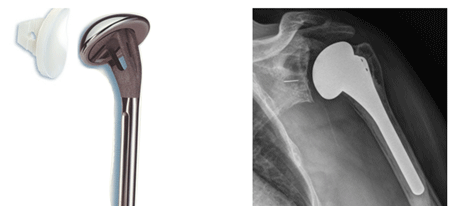

¾î±ú °üÀý(°ß°üÀý)

¾î±ú °üÀýÀº ¿ì¸®¸ö ¿¡¼ °¡Àå ¿îµ¿ ¹üÀ§°¡ ³Ð°í, º´ÀÌ »ý±â¸é ´Ù¸¥ °üÀý¿¡ ºñÇØ ÅëÁõÀÌ ½ÉÇϰí, ¿ÊÀÔ°í ¹þ±â, ¸Ó¸®ºø±â, ÈÀå½Ç °¡±âµî ÀÏ»ó »ýȰ¿¡¼ ¸¹Àº ºÒÆíÇÔÀ» ÁÖ°Ô µË´Ï´Ù. ¶ÇÇÑ °ñ´Ù°øÁõÀÌ ½ÉÇÑ °æ¿ì ³Ñ¾îÁö°Å³ª ÇÏ¸é¼ ¾î±ú¸¦ ´ÙÄ¥ °æ¿ì »ó¿Ï°ñµÎ°¡ ¿©·¯ Á¶°¢À¸·Î Âɰ³Áö´Â °æ¿ì°¡ ÀÖ½À´Ï´Ù. ÀÌ °æ¿ì Á¤º¹À» ½ÃÇàÇÒ °æ¿ì »À°¡ À¯ÇÕµÇÁö ¾Ê°Å³ª °ñÆíÀÌ ±«»ç µÇ´Â °æ¿ì°¡ »ý±â°Ô µÇ¾î Àΰø°üÀý ¼ö¼úÀ» ÇÏ´Â °æ¿ìµµ ÀÖ½À´Ï´Ù.